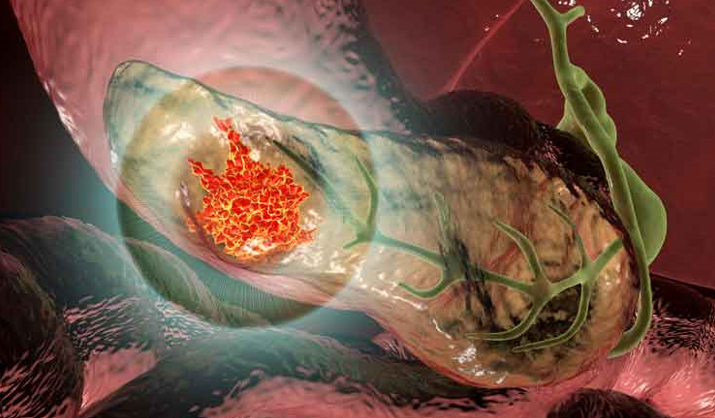

خبر علمیدرمان بیماران سرطان پانکراس با استفاده از واکسن های mRNA شخصی سازی شده

شرکت BioNTech اطلاعات اولیه در مورد اولین مطالعه بالینی فاز اول داروی اینوتراپی برمبنای mRNA (iNeST) را اعلام کرده است که ایمنی و سازگاری خوبی را تاکنون از خود نشان داده است. این دارو از اتوژن cevumeran (معروف به BNT122, RO7198457) همراه با مهارکننده نقاط واررسی ایمنی ضد PD-L1 به نام atezolizumab و همینطور شیمیدرمانی در بیماران مبتلا به سرطان آدنوکارسینومای پانکراس (PDAC) مورد استفاده قرار گرفته است. امکانسنجی پروفایلسازی تومور هر بیمار با هدف طراحی واکسنهای شخصیسازی شده و تولید iNeST در زمان مورد نیاز، مورد تأیید قرار گرفته است. نتایج اولیه حاکی از ایمنی قابل قبول بوده و همینطور نشانگر و امیدوار کننده برای پاسخهای مناسب بالینی است. اتوژن cevumeran پیشرو در طراحی دارویی پلتفورم iNeST در شرکت BioNTech است که همزمان با Genentech عضو خانواده دارویی شرکت Roche در کاربرد درمانی تومورهای جامد به کار میرود. این مطالعه بالینی شامل 19 بیمار است که جراحی را گذرانده و atezolizumab را دریافت کردهاند. از این تعداد 16 نفر (84% بیماران) اتوژن cevumeran را در هفته 9.4 بعد از جراحی دریافت کردهاند. اطلاعات اولیه این 16 بیمار نشان داده است که دریافت این اتوژن با atezolizumab به خوبی در بدن قابل تحمل است. فقط یکی از این 16 بیمار (6%) تب و فشارخون سطح 3 ناشی از دریافت واکسن را از خود نشان داده است. هیچ مورد حساسیت یا درجات دیگری از آن گزارش نشده است. بر اساس این اطلاعات BioNTech و Genentech در حال طراحی یک مطالعه رندوم برای بررسی بیشتر اثرگذاری و ایمنی cevumeran همراه با atezolizumab و شیمیدرمانی در بیماران مبتلا به PDAC هستند. منبع: